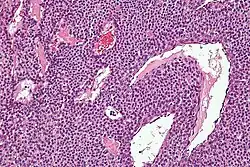

Micrograph of a glomus tumor. H&E stain.

Histologically, glomus tumors are made up of an afferent arteriole, anastomotic vessel, and collecting venule. Glomus tumors are modified smooth muscle cells that control the thermoregulatory function of dermal glomus bodies. As stated above, these lesions should not be confused with paragangliomas, which were formerly also called glomus tumors in now-antiquated clinical usage. Paragangliomas do not arise from glomus cells, but glomus tumors do.